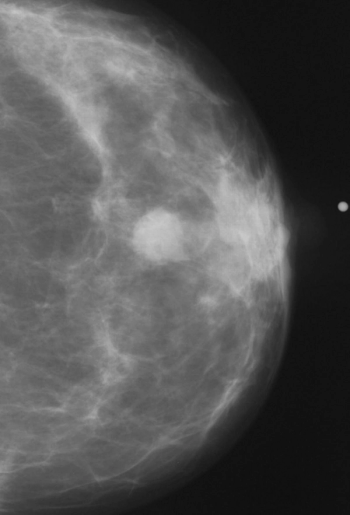

Consistent adherence to the five most recent mammography screenings prior to a breast cancer diagnosis reduced breast cancer death risk by 72 percent in comparison to women who did not have the mammography screening, according to new research findings presented at the annual Radiological Society of North America (RSNA) conference.

An emerging artificial intelligence algorithm, developed to estimate volumetric breast density from 3D-reconstructed digital breast tomosynthesis images, could potentially facilitate individual risk assessments for breast cancer.